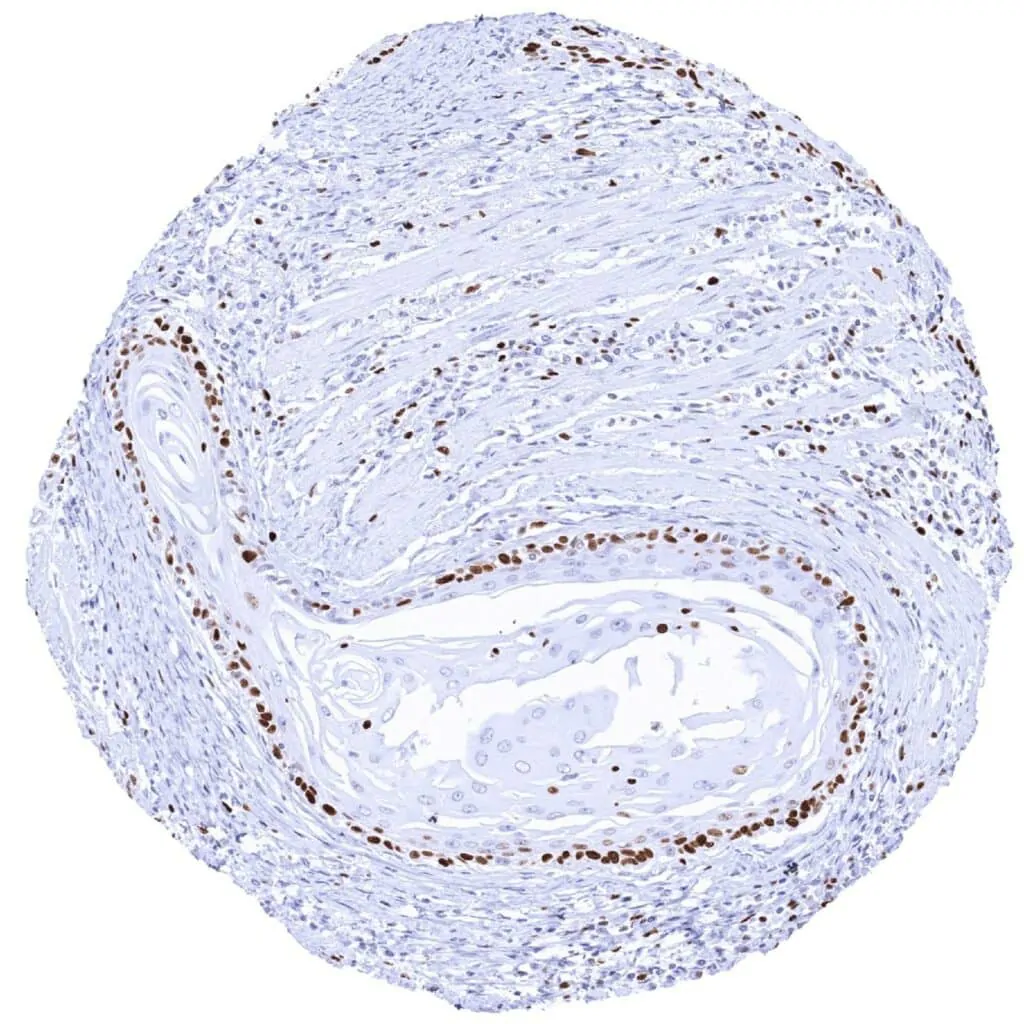

Esophagus – Squamous cell carcinoma with strong MCM2 staining of peripheral tumor cells